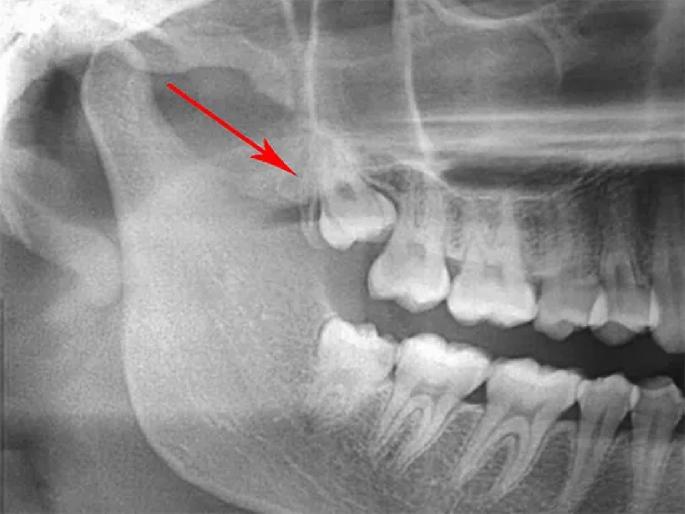

नागपूर : कोरोनातून बाहेर पडत नाही तोच ४३ वर्षीय रुग्णाला गंभीर स्वरूपाचा म्युकरमायकोसिस झाला. शस्त्रक्रिया करून वरचा जबडा काढावा लागला. अशा स्थितीत शासकीय दंत महाविद्यालय व रुग्णालय त्यांच्या मदतीसाठी धावून आले. अथक परिश्रमाने कृत्रिम जबडा तयार केला. त्याच्या प्रत्यारोपणाची अत्यंत गुतागुंतीची शस्त्रक्रियाही यशस्वी केली. म्युकरमायकोसिसनंतरचे हे पहिलेच जबडा व दंत प्रत्यारोपण ठरले. सध्या रुग्णालयाकडे ७० रुग्ण या प्रत्यारोपणाच्या प्रतीक्षेत आहेत.

पांढरकवडा येथील सूरज जयस्वाल याच्या म्युकरमायकोसिसच्या निदानानंतर त्यावर शस्त्रक्रिया करीत वरच्या जबड्याचा काही भाग काढला. टायटॅनियम धातूद्वारे कृत्रिम जबडा तयार केला. यासाठी एका खासगी कंपनीने मदत केली. आता जबड्यात कृत्रिम दात बसविण्याची प्रक्रिया होणार आहे.